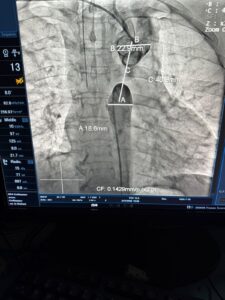

وأوضح «عبدالغفار» أن الفريق الطبي بمستشفى مبرة مصر القديمة، نجح أيضا في إجراء عملية تغيير الصمام الأورطي عن طريق القسطرة بتقنية (تافي)، لمريض عمره 69 عاماً، يعاني من ضيق شديد بالشريان الأورطي النازل، حيث تم تغيير الصمام ثم عمل توسيع للشريان الأورطي وتركيب دعامة، وهي من العمليات الدقيقة جدا، مشيرا إلى أن الطاقم الطبي نجح في علاج 37 مريضا بواسطة هذا التدخل شديد التعقيد .